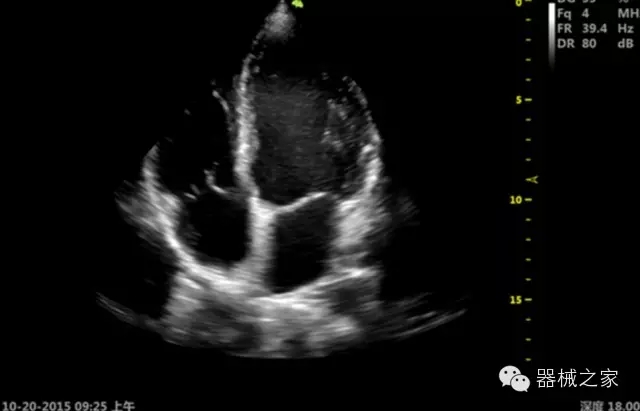

品牌:開(kāi)立(SONOSCAPE)

經(jīng)典產(chǎn)品:S8EXP

臨床圖片賞析

產(chǎn)品特點(diǎn)

·心功能綜合指數(shù)(TEI指數(shù)):用于左、右心室整體心臟收縮舒張功能評(píng)估的測(cè)量方法;

·全方位可調(diào)M型:有利于更好的觀察心腔大小及室壁階段性運(yùn)動(dòng)的異常情況;

·組織多普勒成像(TDI):TDI可定量評(píng)價(jià)心肌運(yùn)動(dòng),判斷是否有局部病變,還可評(píng)價(jià)早期的舒張功能;